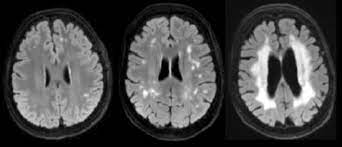

Fazekas 1 мрт что это

Fazekas 1 мрт что это 109 фотографий